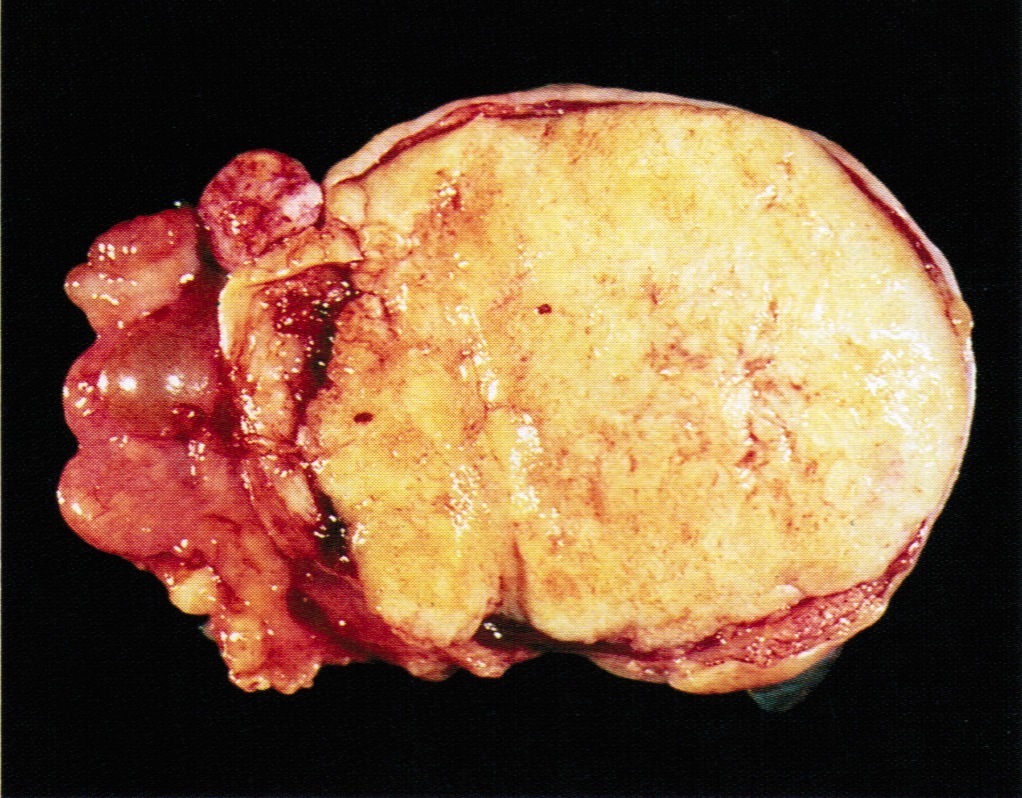

Gross description

- > 95% unilateral and confined to the ovary

- Variable size, average 10 - 12 cm

- Encapsulated with smooth lobulated surface, tan or yellow (depending on the degree of luteinization and lipid content), soft to firm (depending on the amount of fibromatous component), usually solid and cystic with straw colored or mucoid fluid, can have areas of necrosis and hemorrhage

- The more luteinized tumors are more yellow / orange

- May resemble serous cystadenoma

- Rare androgenic tumors tend to be large with thin walled cysts (Arch Pathol Lab Med 1984;108:786)